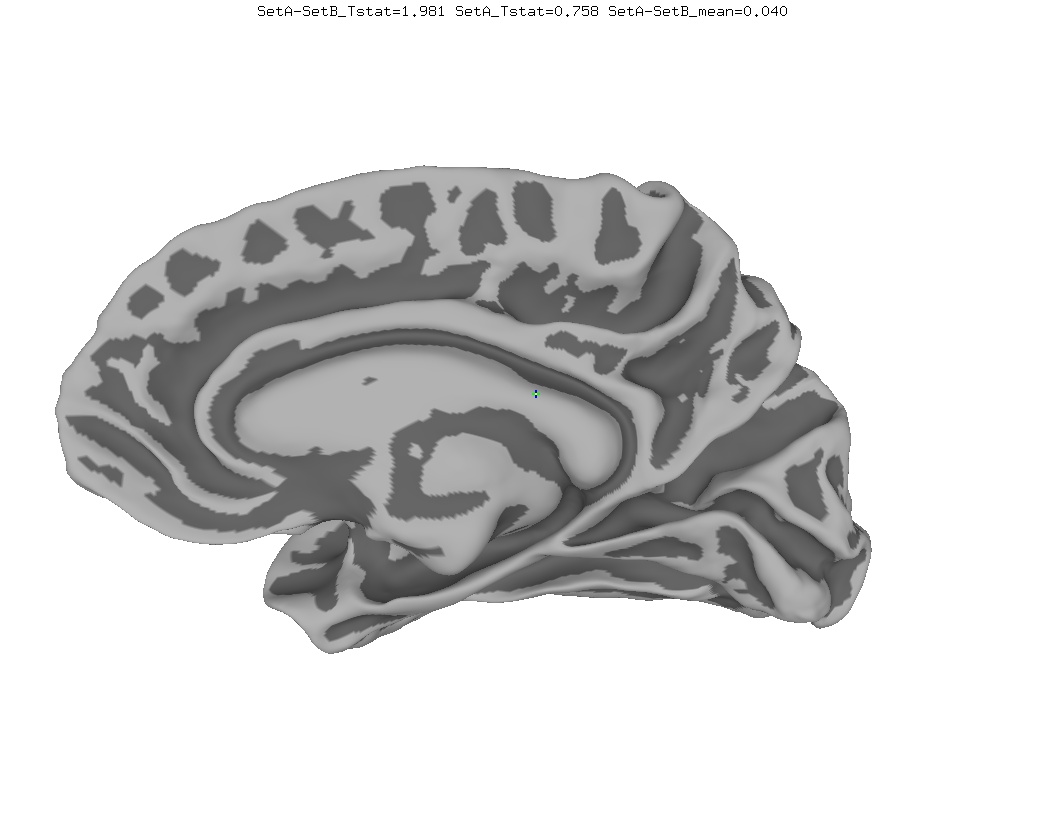

Functional Data

Functional data of the Mouth vs. Eye contrast mapped to the average surface. It is hard to quantify the difference, but one way is to compare the maximum statistical values; with better intersubject alignment, these would presumably increase.

- NEW: Max t-value for Mouth: 9.3 Eye:10.1 Eye vs Mouth: 5.6

- OLD: Max t-value for Mouth: 7.9 Eye:8.8 Eye vs Mouth: 5.8

data from Zhu LL, Beauchamp MS. Mouth and Voice: A Relationship between Visual and Auditory Preference in the Human Superior Temporal Sulcus. Journal of Neuroscience 8 March 2017, 37 (10) 2697-2708; DOI: https://doi.org/10.1523/JNEUROSCI.2914-16.2017. Click here to download the PDF. Surface averages were not used in this paper so the bug did not affect the published results.

New

Old